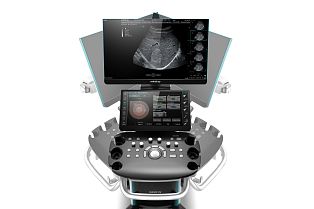

УЗИ аппарат Mindray DC-90 X-insight

Аппарат Mindray DC-90 основан на архитектуре X-Insight и спроектирован с учетом наиболее востребованных технологий, необходимых для проведения исследований у женщин, в том числе во время беременности. Обладает поддержкой таких базовых акушерских опций, как Smart 3D, Smart OB, Smart NT, а так же следующих продвинутых функций для высокого уровня диагностики врожденных пороков развития, Smart Planes CNS, Smart Planes Fetal Heart, iLive Pro, iPage Plus, SCV Plus, STIC, Niche/3Slice. Аппарат Mindray DC-90 - флагман в линейке стационарных аппаратов DC, построен на платформе X-Insight.

Производитель позиционирует эту систему, в большей степени, как предназначенную для исследований в области женского здоровья, хотя по сути она является универсальной машиной и подходит для ультразвуковых исследований не только в гинекологии и акушерстве, но и, например, в кардиологии и общей диагностике.

Преимущества и технологии

Основные преимущества новой системы заключаются в улучшенном «двойном» процессоре и такой технологии как iClear+ - это адаптивный режим шумоподавления второго поколения (при том, что во всех других моделях серии DC есть в базе этот же режим первого поколения). Так же, благодаря улучшенному процессору, система предлагает чуть лучшую визуализацию в 3D/4D режимах.